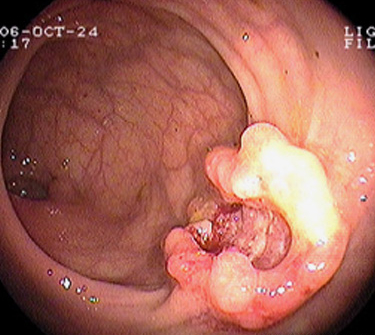

In den meisten Fällen entwickelt sich ein Darmkrebs aus einem zunächst gutartigen Dickdarmpolypen, auch Adenom genannt. Bei 10% der Darmkrebsfälle sind genetische Faktoren beteiligt, welche die Entstehung eines Krebses begünstigen.

Bei Verdacht auf Darmkrebs untersucht der Arzt zunächst den Stuhl auf verborgenes Blut (okkultes Blut) und tastet den Enddarm aus. Auch bei fehlendem Blutnachweis im Stuhltest und normalem Befund der Tastuntersuchung des Mastdarms ist bei weiter bestehendem Verdacht eine Darmspiegelung (Koloskopie) angesagt.